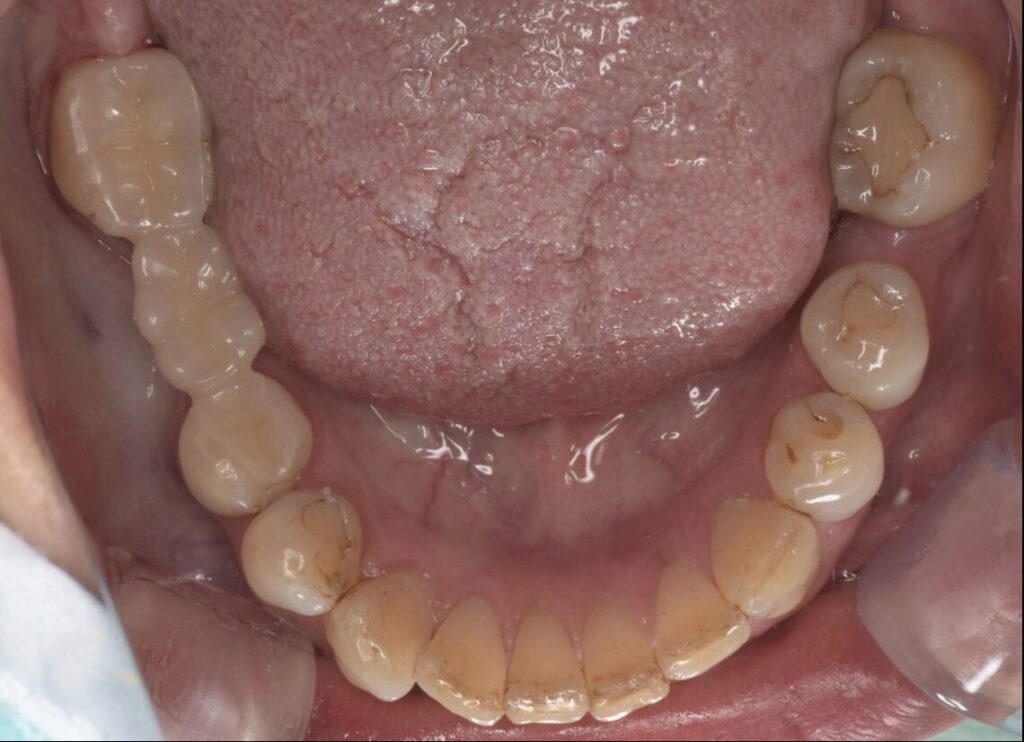

初診時

形成後

セラミックSET後